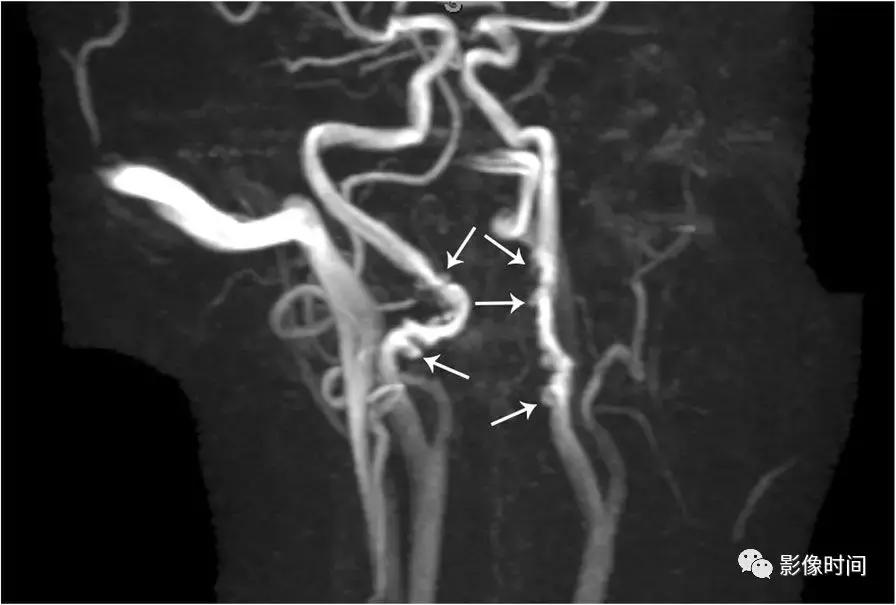

模式图显示纤维肌性发育不良的主要亚型:1 型表现为收缩和扩张的交替;2 型表现为管状狭窄,3 型表现为局灶性波纹+憩室。MRA 显示双侧颈内动脉「串珠」外观(箭头)。CTA 和 DSA 亦显示颈内动脉「串珠」外观。